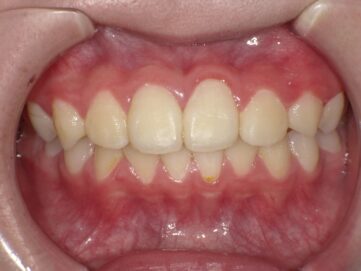

顎顔面矯正治療とは、歯並びだけでなく噛み合わせや顎関節を考慮して行う矯正治療のことです。顎顔面矯正治療により、顎関節症の緩和や鼻づまりの改善効果も期待できると言われています。主に、小児期に行い、見た目をよくするだけではなく、顎の骨や顔の骨格を正しい形に導きます。

歯並びの悪い原因としては顎の急な成長によるものが多く、装置で顎を広げる事で歯が綺麗に並ぶスペースを確保します。

青島歯科クリニックでは、顎顔面矯正治療によるお子さまの歯並びを綺麗に整える治療を行っており、お子さまの歯並びを骨格から正しく治し、成長を一緒にサポートさせて頂いております。

■対象年齢:5~12歳

■治療期間:2~3年